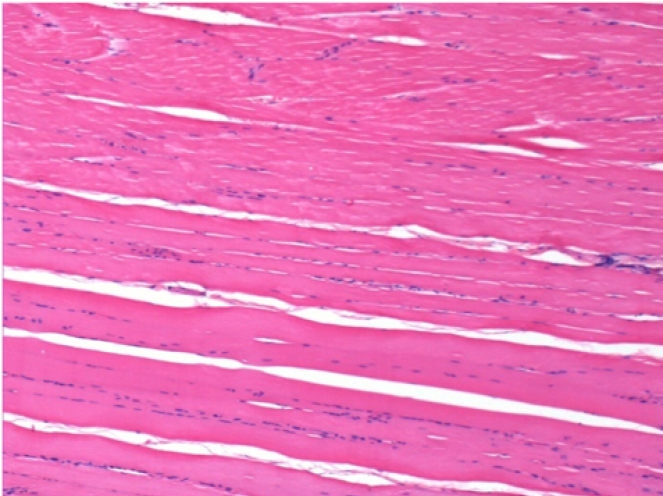

7 місяців (210 днів) після ін'єкції 0,1 мл Ендопіл в правий претибіальний м'яз.

Повна Restitutio ad integrum через 7 місяців

Л :Контроль 50x210 днів

П:50X-210 днів